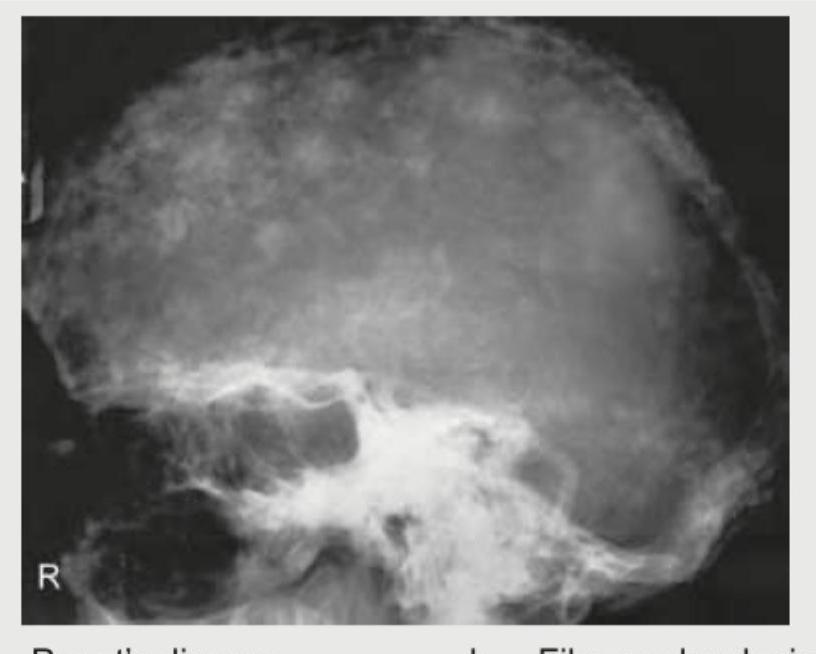

Question 14: A 65-year-old man presents with bone pains. X-ray Skull shows? (Recent NEET Pattem 2018-19)

- A. Paget's disease

- B. Fibrous dysplasia

- C. Histiocytosis-X

- D. Multiple myeloma (Correct Answer)

Explanation: ***Multiple myeloma*** - The X-ray shows multiple, well-defined, lytic lesions (''**punched-out lesions**'') scattered throughout the skull, which is highly characteristic of multiple myeloma. - This condition is a **plasma cell malignancy** that commonly affects older adults and often presents with **bone pain** due to osteolytic activity. *Paget's disease* - Characterized by abnormal bone remodeling, leading to bone enlargement, thickening, and a **"cotton wool" appearance** on X-ray, which is not seen here. - While it can cause bone pain and skull involvement, the lytic pattern in the X-ray is not typical for Paget's disease. *Fibrous dysplasia* - This condition involves **normal bone marrow** being replaced by **fibrous tissue** and immature bone, often presenting as a **ground-glass appearance** or expansile lesions, usually in younger individuals. - The distinct "punched-out" lesions seen in the image are not characteristic of fibrous dysplasia. *Histiocytosis-X* - Also known as Langerhans cell histiocytosis, it can cause **lytic bone lesions**, particularly in the skull, described as a **"map-like" or "geographic" pattern**. - Although it causes lytic lesions, the pattern in the image, with its numerous small, widespread lytic lesions, is more indicative of multiple myeloma in an older adult.